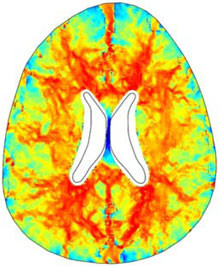

A numerical finite element model of one human brain is built in COMSOL in order to study a particular form of hydrocephalus, the so called Normal Pressure Hydrocephalus (NPH). The geometry of the ventricles and the skull is obtained by Magnetic Resonance Imaging (MRI) and imported in ... Read More